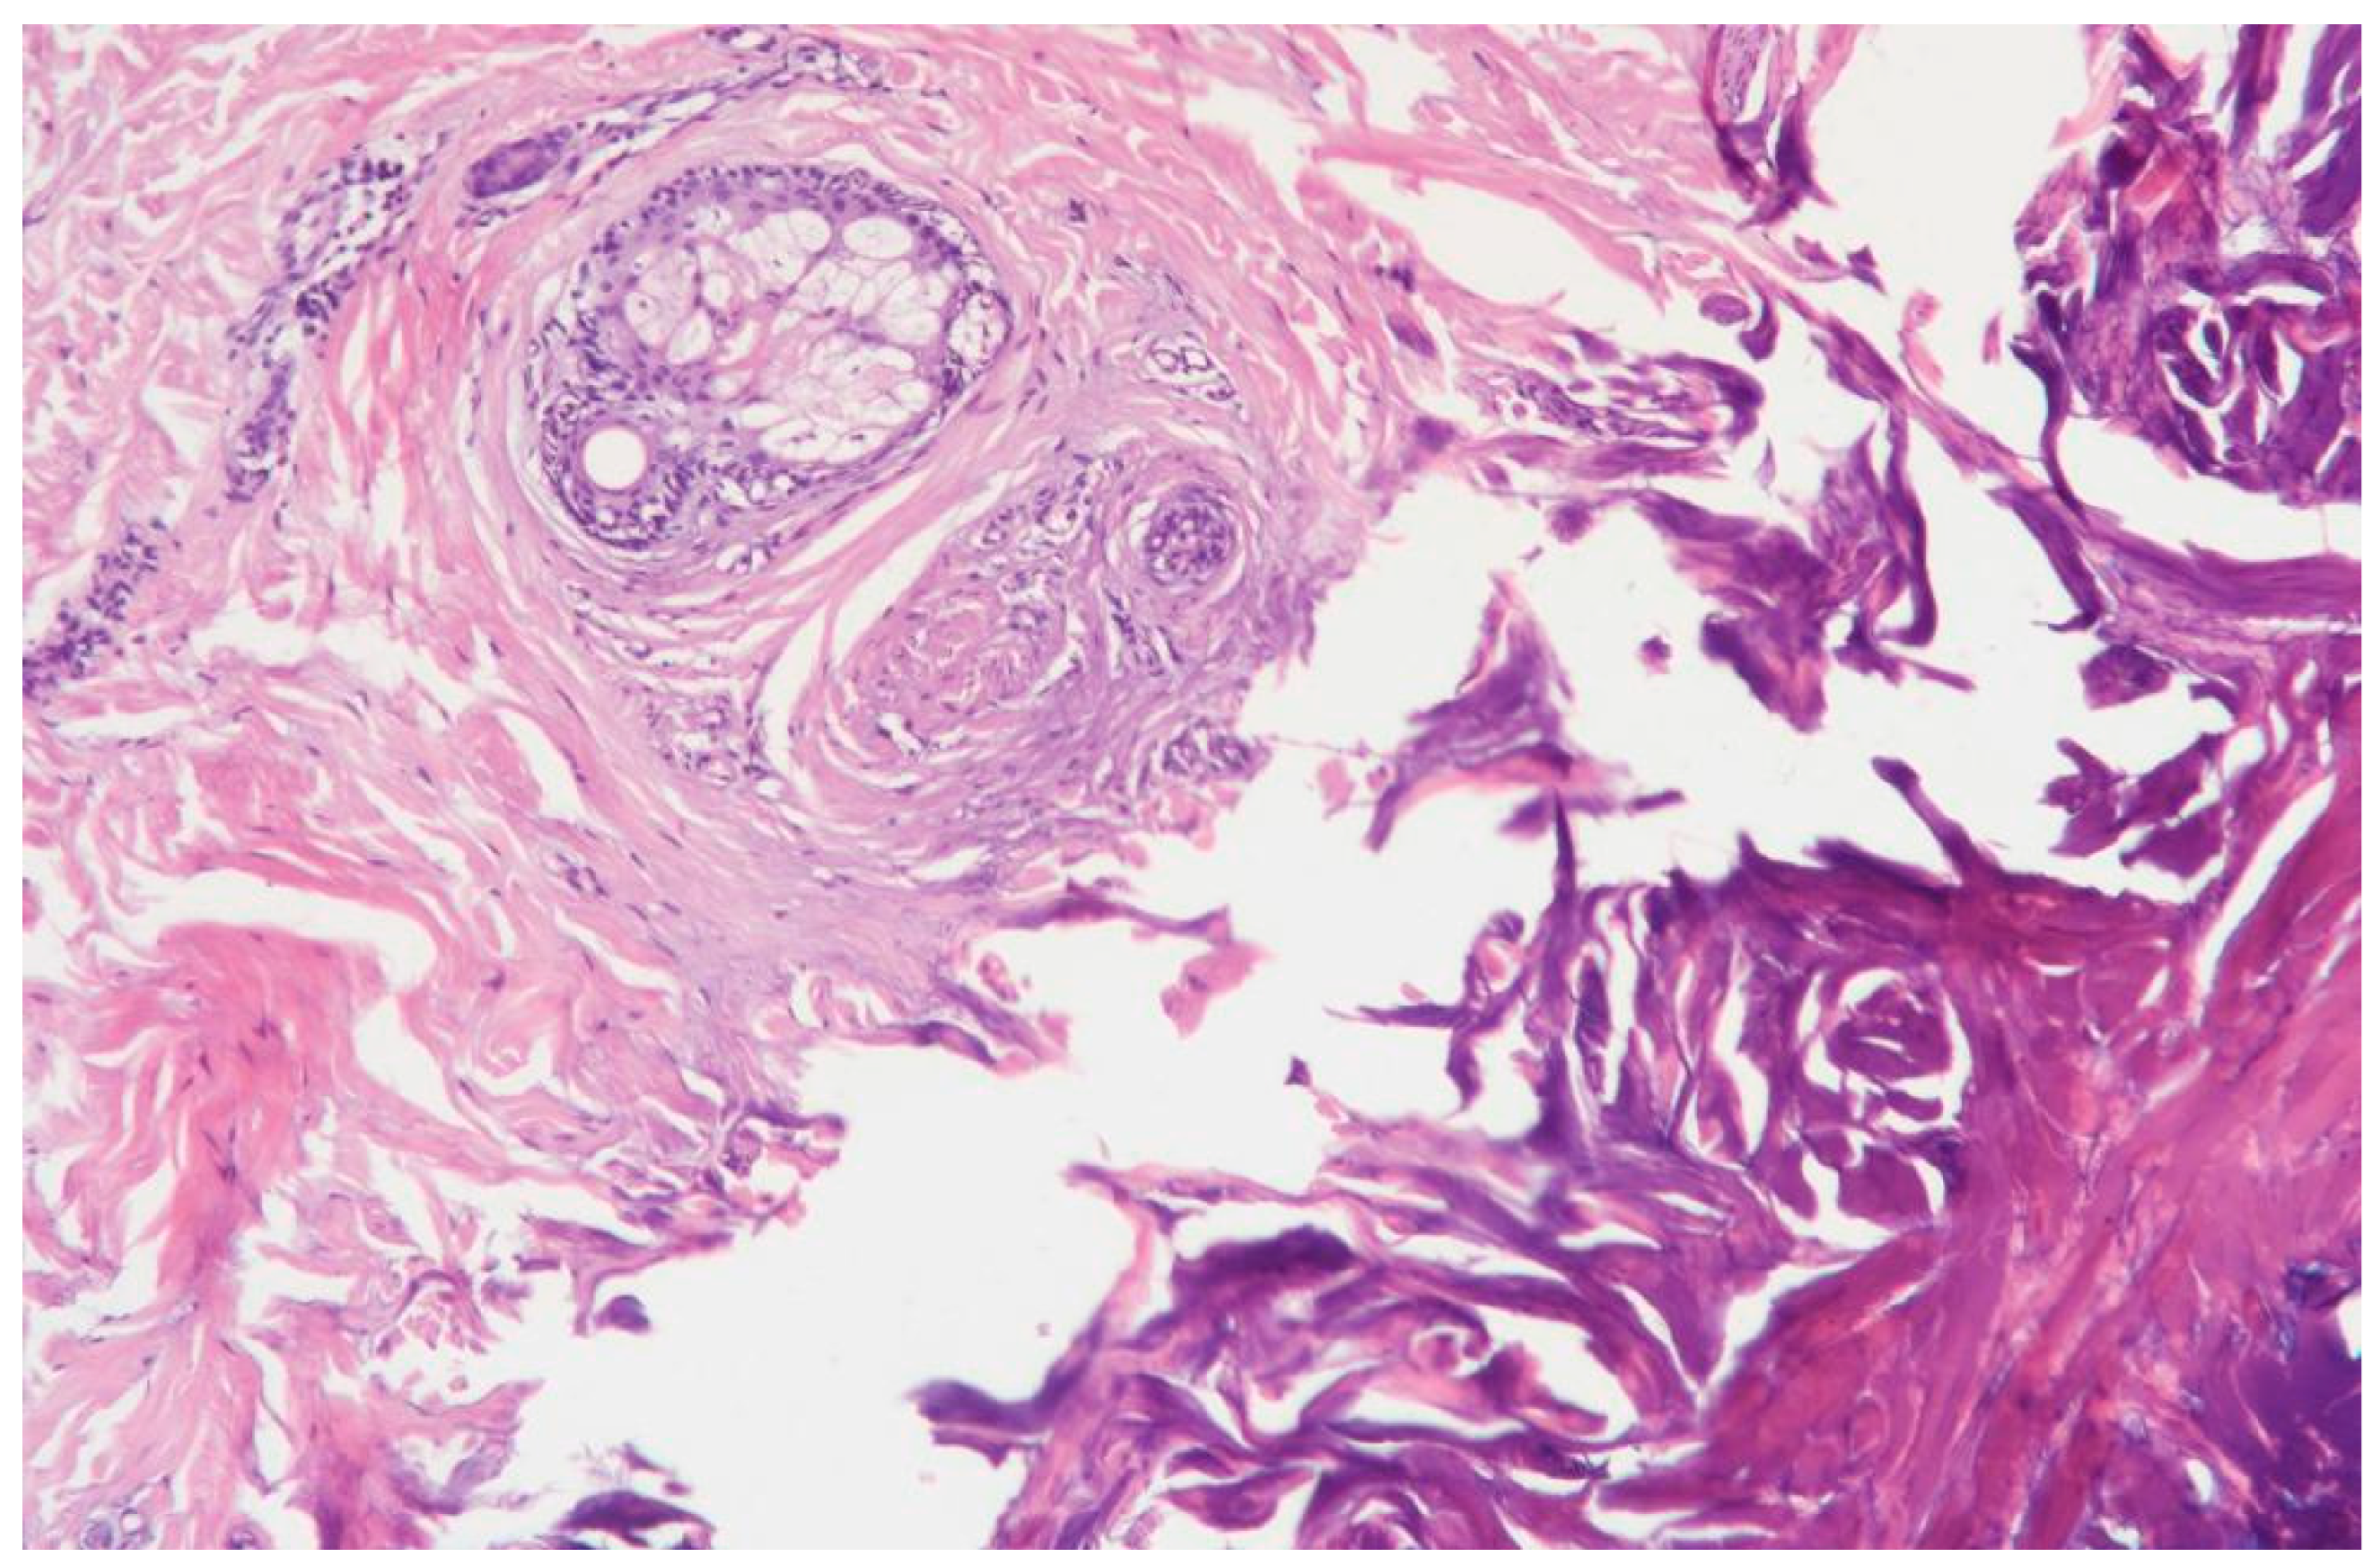

3.1.2. Clinical Case 2: Soft Tissues in the Dissection Area, 15 W (See Figure 3)

Description: During the histological examination, the epidermis and dermis were found to be in a state of subtotal necrosis, with the formation of a demarcation zone infiltrated abundantly with polymorphonuclear leukocytes. The infiltrate extended into the subcutaneous adipose tissue. The vessels in the necrotic area were coagulated, while those in the underlying tissues were markedly dilated. There were no signs of hemorrhage. The appendages of the underlying skin tissues remained intact, and the collagen fibers were preserved.

Figure 3.

Skin changes in Rat 1 on the 7th day after exposure to the thulium laser at 15 W, 75 Hz. H&E staining, 10× objective magnification.